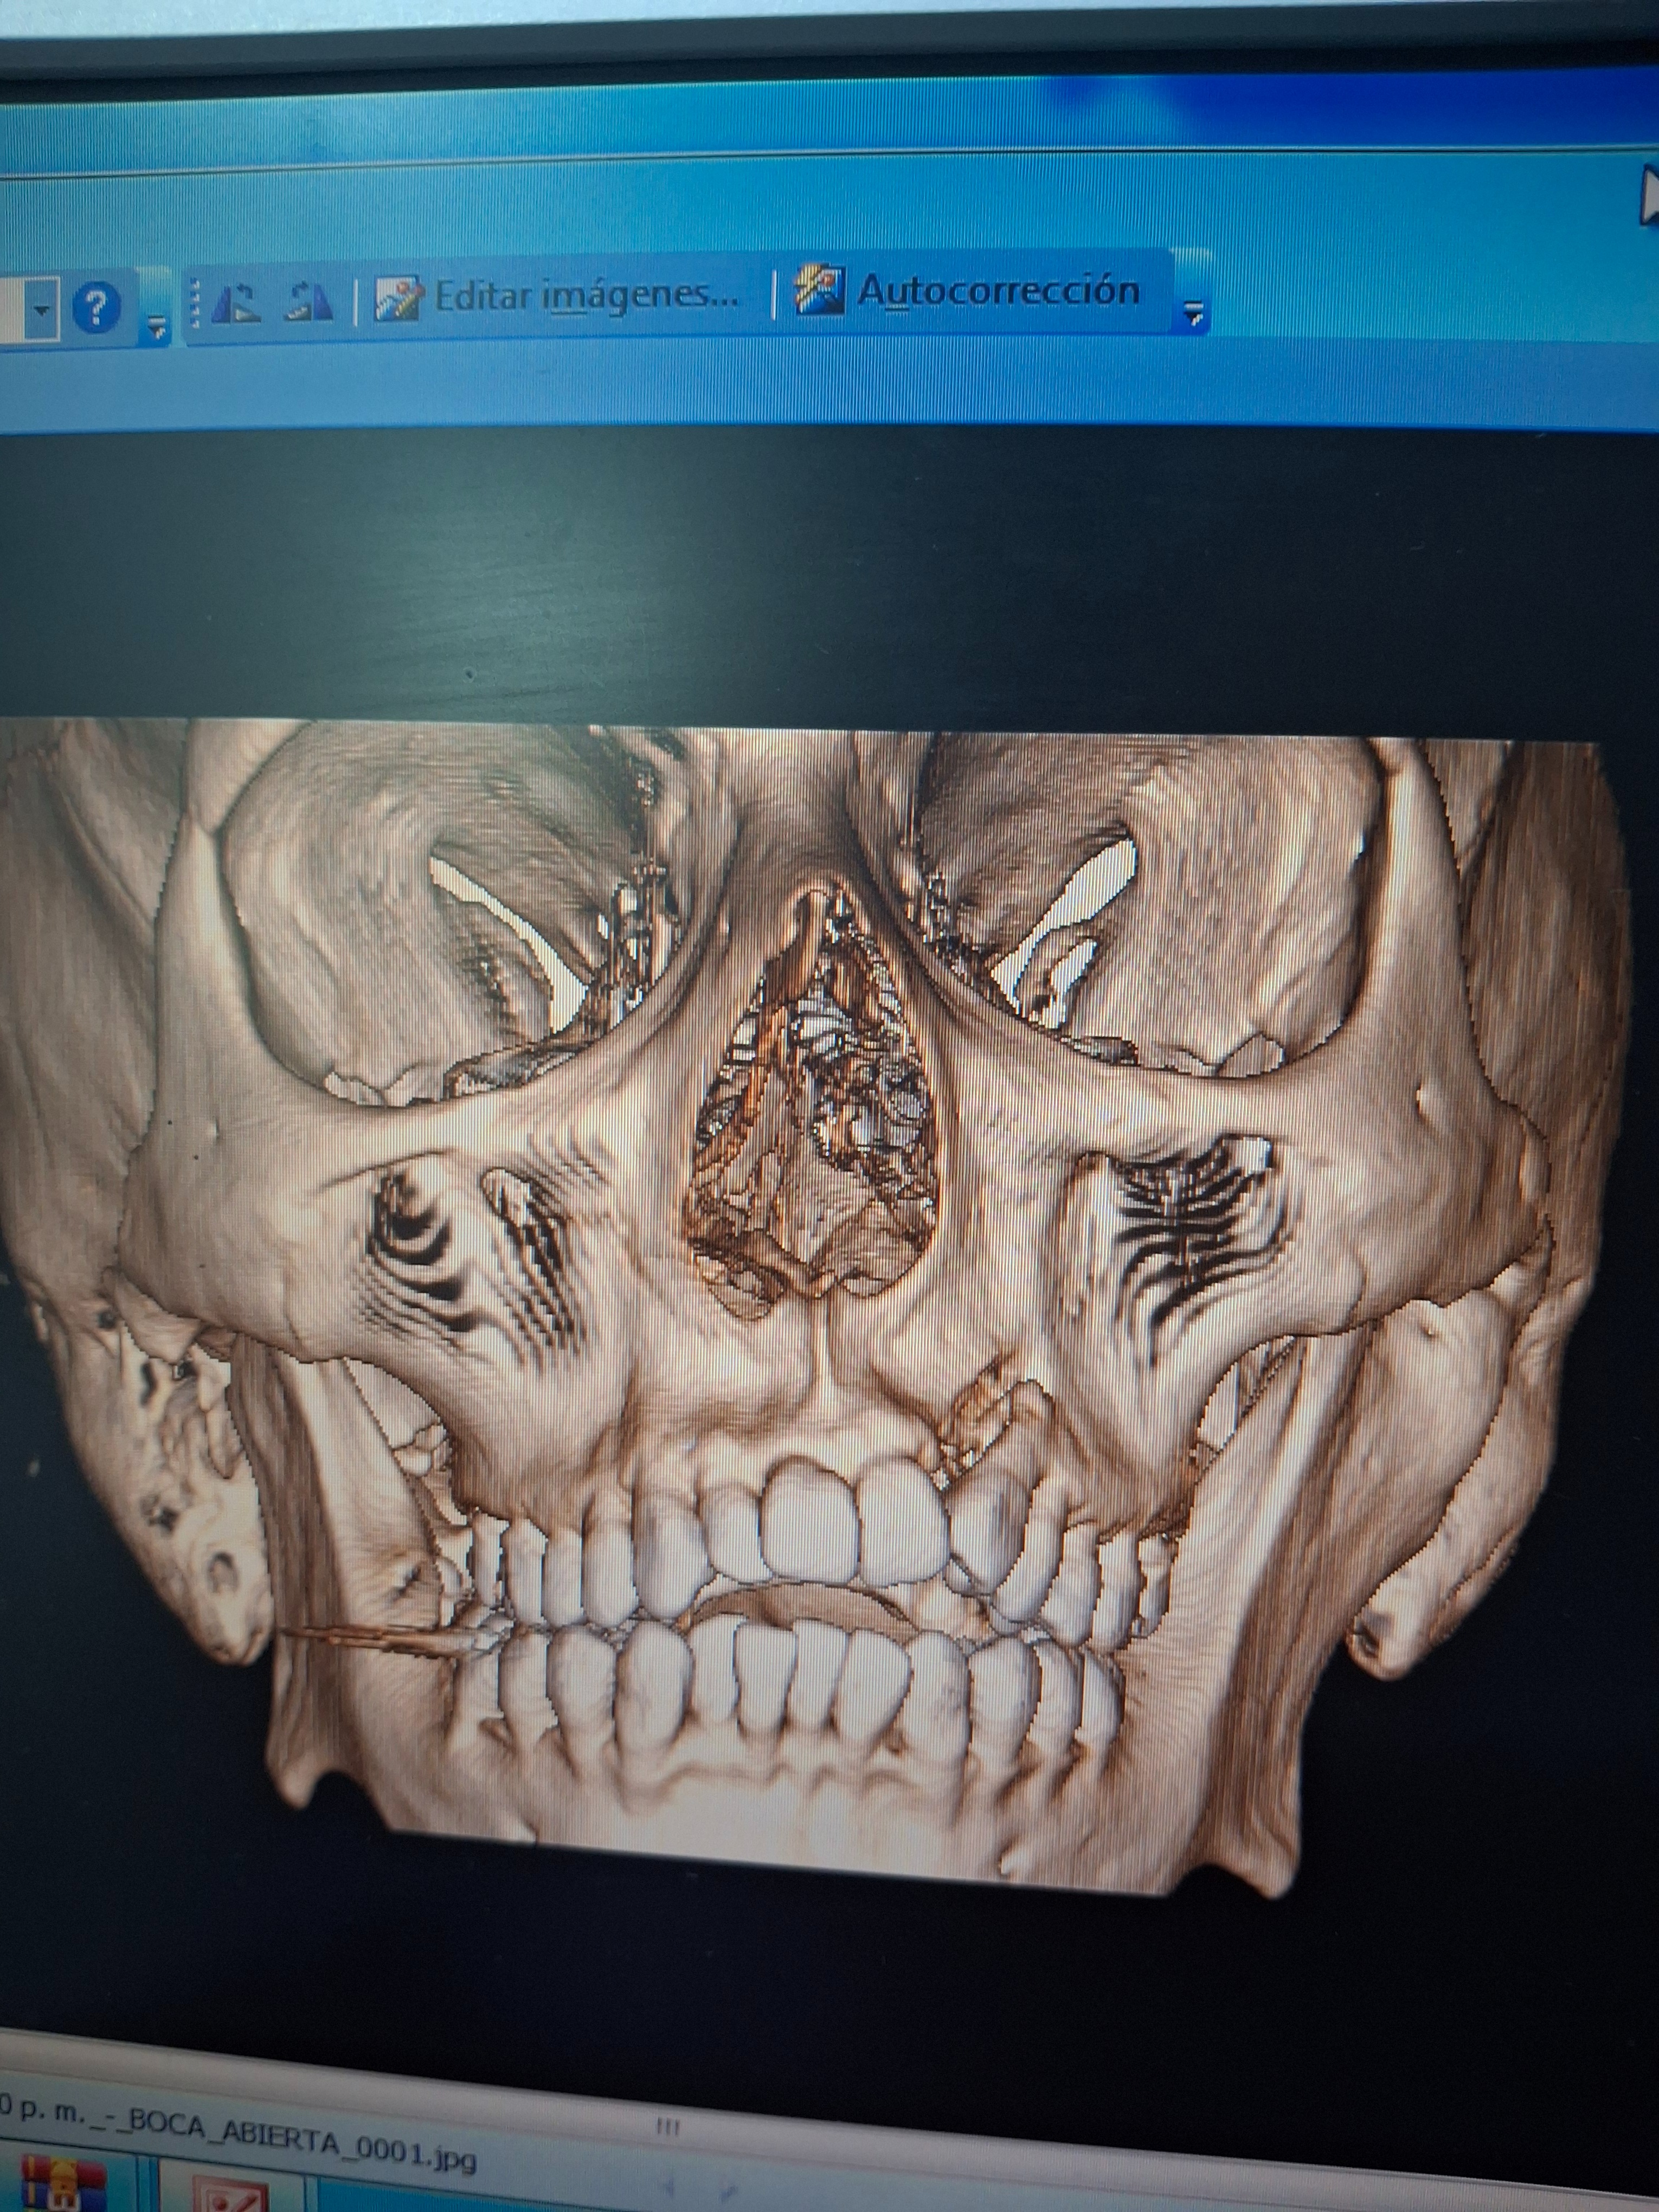

En 2020, se confirmó la implacable verdad: los huesos estaban fusionados. Padecía una anquilosis mandibular total. Me sometí a una cirugía compleja donde cortaron la fusión e implantaron músculo para evitar el contacto. ¡Pareció un éxito! Pero mi alegría fue fugaz. Los huesos, con una tenacidad espeluznante, se volvieron a unir, creando una densa "bola de hueso" en mi lado izquierdo.

Hoy, mi apertura bucal es de apenas 1 milímetro. Llevo años condenado a comer solo líquidos, puré y cosas que sean muy blandas, cuando lo ideal y normal en todo ser humano, es el disfrute del simple y glorioso placer de un bocado crujiente. Es una tortura psicológica. Ver a otros comer me inflige una frustración profunda, y las miradas inquisitivas de la gente en público han alimentado noches enteras de depresión y soledad. Solo anhelo la dignidad de comer una comida normal.

Los médicos han sido claros: necesito urgentemente una prótesis de ATM para que los huesos nunca vuelvan a tocarse. Es la única forma de recuperar mi capacidad de masticar, de sonreír sin restricciones y, poder comer como una persona común y corriente.

In 2020, the relentless truth was confirmed: the bones were fused. I was suffering from total mandibular ankylosis. I underwent a complex surgery where they cut the fusion and implanted muscle to prevent contact. It seemed like a success! But my joy was short-lived. The bones, with terrifying tenacity, fused together again, creating a dense "ball of bone" on my left side.

Today, my mouth opening is barely 1 millimeter. For years, I have been condemned to eat only liquids, purées, and very soft things, when the ideal and normal thing for any human being is the enjoyment of the simple and glorious pleasure of a crunchy bite. It is psychological torture. Watching others eat inflicts a deep frustration upon me, and the inquisitive stares from people in public have fueled entire nights of depression and loneliness. I only long for the dignity of eating a normal meal.

The doctors have been clear: I urgently need a TMJ prosthesis so that the bones never touch again. It is the only way to recover my ability to chew, to smile without restriction, and to eat like an ordinary person.